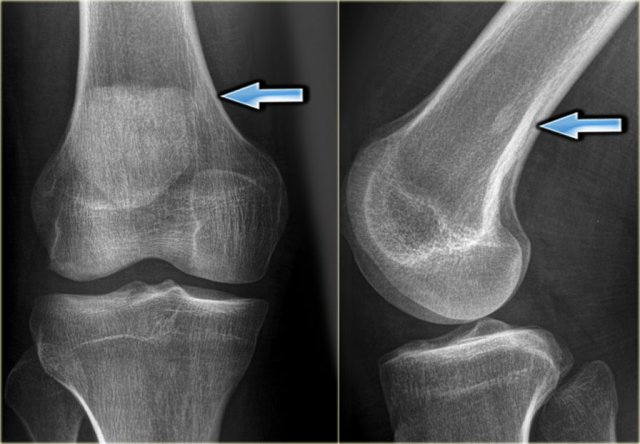

Chondrosarcoma (4)

On the left a chondrosarcoma in the proximal tibia diaphysis.

The tumor is recognized by subtle calcifications in the proximal part.

The distal border is not well defined.

Notice endosteal scalloping at the medial side which is a hallmark of chondrosarcoma.

MR better defines the extension of the lesion.

MRI also demonstrates the endosteal scalloping.